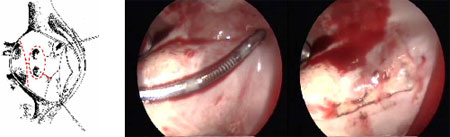

Radyofrekans Ablasyon yönteminin uygulamasının kolaylığı nedeni ile Maze Operasyonlarının yerini alması beklenmektedir. Maze operasyonlarındaki sayısız kesiler yerine Boston Scientific tarafından üretilen radyofrekans jeneratöründen elde edilen dalgalar ile sol atrium içinde bilerlenen hatlar 2 dakika yakılarak skar dokusu yaratılarak atrial fibrilasyonun kaotik ileti yolları düzene sokulmaktadır. İşlem sonunda sol atrium içeriden dikilebilir, dışarıdan bağlanabilir veya kesilerek dikilebilir. İşlem kapak takılmadan önce yapılmaktadır.

Radyofrekans probunun uygulanmasından sonra olusan skar dokusu.